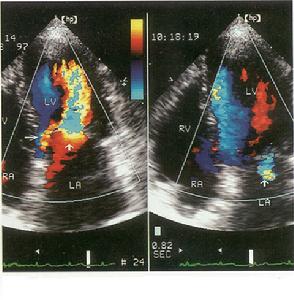

竇性停搏心肌診斷檢查